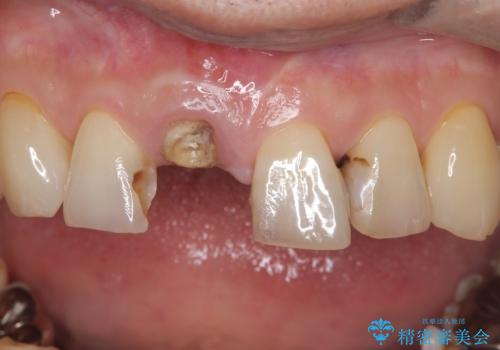

- 右上の前歯(1番)が折れたことを主訴に来院されました。診察とレントゲン検査の結果、歯冠の大部分が失われ、歯根の先には根尖病変(膿の袋)も認められました。残存歯質がほとんどなく、歯を保存することが困難と判断し、抜歯が必要と診断しました。

前歯は見た目の印象に大きく関わる部位であるため、できる限り治療期間中の審美性と機能性を損なわないことが求められます。患者さんとも相談のうえ、抜歯と同時にインプラント体を埋入する「即時埋入インプラント」を選択しました。これにより治療期間の短縮と、歯ぐきや骨の形態を保ちながらの審美的回復が可能となります。

治療は、まず感染の原因となっていた前歯を慎重に抜歯し、抜歯と同時にインプラントを埋入しました。審美性を重視する部位であるため、骨や歯ぐきのボリュームを維持するための補填処置も併用しています。術後は仮歯を装着し、見た目を保ちながらインプラントと骨がしっかりと結合するのを待ちました。